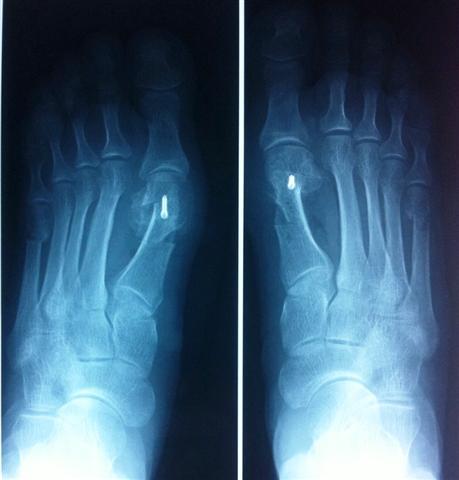

Мы в своей практике достаточно давно ушли от обычных экзостозэктомий (иссечения костного нароста- пресловутой шишечки или косточки) и операций только на мягких тканях (восстановление и сопоставление связок вокруг первого плюснефалангового сустава (места соединения большого пальца стопы с плюсневой костью)), с целью нормализации поперечного свода стопы в нашей клинике применяется система малоинвазивных операций, разработанная одним из апологетов хирургии переднего отдела стопы французским ортопедом L.Barouk. Операция заключается в многоплоскостных остеотомиях (пересечение кости) плюсневых костей с целью воссоздания поперечного свода стопы. Смещенные фрагменты плюсневых костей под рентген-контролем при помощи современного электронно-оптического преобразователя, фиксируются специальными внутрикостно устанавливаемыми мини-винтами, не требующими в дальнейшем их удаления.